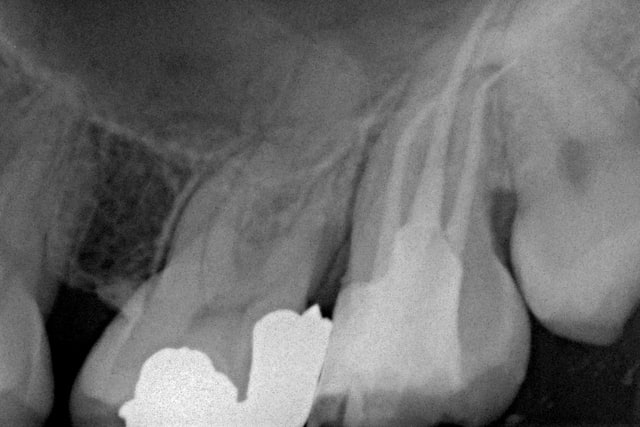

Je commence avec ce bout de F2 que j'ai ostéointégré :( à l'extrémité de la racine Distovestibulaire de cette 17. A l'origine, un "buggage" du localisateur d'apex. Je ferai dorénévement tout de meme une petite rvg de controle....